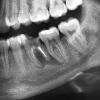

unogirlie Опубликовано 23 декабря, 2009 Поделиться Опубликовано 23 декабря, 2009 Здравствуйте!У меня такая ситуация: пошла весной к зубному, где обнаружили по снимку восполение под зубом (внизу 6, левая часть челючти)! Ставили лекарство 3 раза и вот совсем свежий снимок, но но по-моему ничего не изменилось. Врачь говорит удалять, пока восполение не разрослось дальше, но ужасно не хочется в молодом возрасте такое сотворить с зубиком! В общем сам зуб хороший, но вот под ним... Он никогда не болел, единственное, что изредка сбоку из десны выходил гной, но это не создавало огромной проблемы, перетерпела день и все! На фото в канале остатки лекарства. Спасибо всем за ранее! Ссылка на комментарий

Ion Опубликовано 23 декабря, 2009 Поделиться Опубликовано 23 декабря, 2009 Конечно зуб можно спасти, а также Вам надо найти хорошего врача который бы сделал ещё раз ревизию каналов. Воспалилась 6 -ка, а также надо лечить и 7-ку , тоже есть воспаление. А на 6-ке , медиальный канал вообще только на половину обработан. После лечении 6 зуба, затем желательно закрыть его коронкою. Обьязательно найдите хорошего врача, который умеет на самом деле делать механич. и мед.обработки каналов и знает по-современному лечить каналы. Ссылка на комментарий

Fred Опубликовано 23 декабря, 2009 Поделиться Опубликовано 23 декабря, 2009 Она там тыкала иголочками, что я чувствовала, правда сильной боли не было...А возможно, что лекарство вообще не стекало по каналу до восполения? (последний раз ставили лекарство в сентябре!)Значит, вы считаете, что лучше как следует прочистить каналы до конца и запломбировать?? а это действительно оправдано в моем случае?? а то ведь там 7 зуб близко к воспалению! "Лекарство" для зуба - это качественная канальная пломба. Никаких веществ закладывать в каналы не надо, тем более закладывать так, чтобы они касались очага воспаления. Воспаление - это реакция Вашего организма на что-то плохое в канале. Устрани его, предотврати возможность накопления этого плохого снова, а остальное залечит организм. Не только в Вашем случае, но и во всех случаях лечения каналов нужно стараться всеми силами пройти каналы до их концов и плотно запломбировать. Вот это и есть лекарство. В Вашем случае, если смотреть на данную картинку, ситуация стандартная, может только очаг воспаления великоват. Это означает, что до полного заживления может пройти и года два, но случай банальный и легко решаемый, если там еще чего-то плохого натворить не успели. Ссылка на комментарий

Fred Опубликовано 25 декабря, 2009 Поделиться Опубликовано 25 декабря, 2009 Вы знаете, она мне там еще маааленький кусочек иголочки оставила, пыталась вытащить всеми силами, но поскольку канал очень кривой, то она его не достала и вообщем-то этот канал до конца не прошла, т.к. она побоялась еще там оставить иголки. Может из-за этого такое восполение не проходит!? Я вот готова его попробовать вылечить, но не получиться ли так, что восполение поползет на 7 и 8 зуб и тогда придется лечить уже все три зуба!? И можно ли сделать какие-нибудь уколы прямо в десну с антибиотиком, например?? Была мысль об этом спросить, так как в одном корне у Вас более четкий контраст, чем положено быть "лекарству". Видимо, этот кусок иголки блокирует канал, и не получается пройти глубже, где залегают нечистоты. Кстати, место, где залегает этот обломок, достаточно благоприятное, и удалить ее не должно составить большого труда.До 8 зуба воспаление не дойдет, но 7 может и может затронуть, уже сейчас есть некоторые подозрения ... Ссылка на комментарий